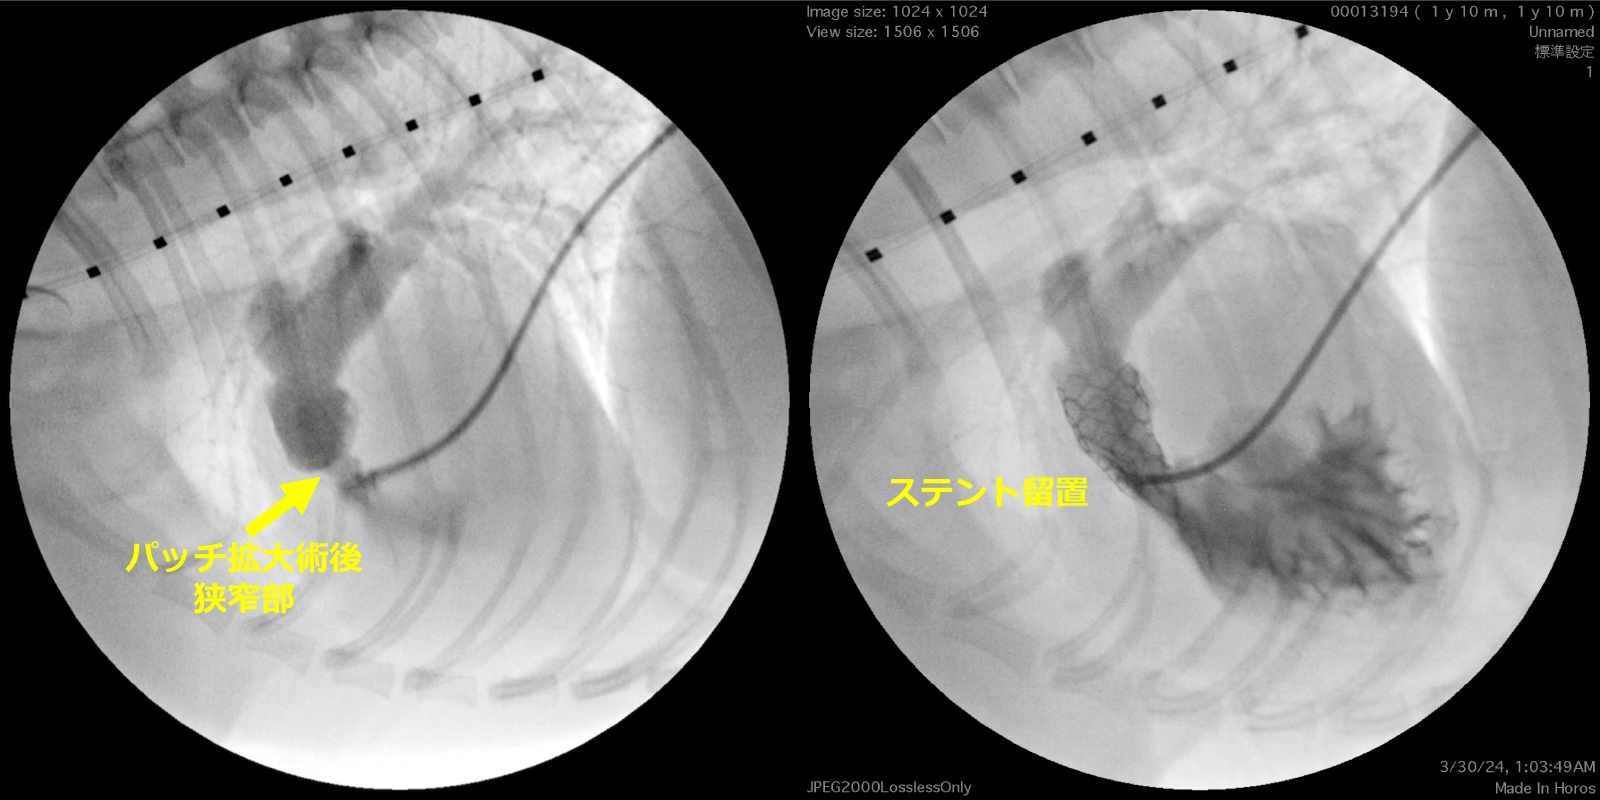

バルーンのスリッピングなどもなく、

狭窄部位に対するバルーンのくびれ消失を確認

ステント留置後、運動不耐性は改善された

異常隔壁を全て除去することで隔壁孔を

4.3mm→9.0mmに拡張

ステント留置後、臨床症状の改善を確認